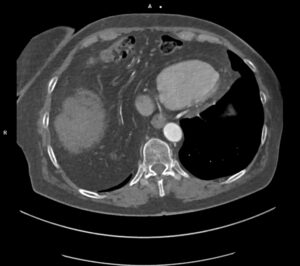

Figurile 3 şi 4: axial CT în timp venos torace şi abdomen superior

Discuţie caz nr 127: se evidențiază hernierea intratoracică a jumătății distale a colonului ascendent, unghiului hepatic al colonului și a unei părți din colonul transvers printr-un orificiu herniar situat anterior de partea dreapta împreună cu o parte din mezocolon.

DE LUAT ACASĂ!!! Hernia Morgagni este una dintre herniile diafragmatice congenitale și este caracterizata de hernierea prin foramenul Morgagni. În comparație cu herniile Bochdalek, herniile Morgagni tind să fie: localizate anterior, mai des pe partea dreaptă ( aproximativ 90%), mici, rare aproximativ 2% din herniile diafragmatice congenitale), cu risc scăzut de prolaps.